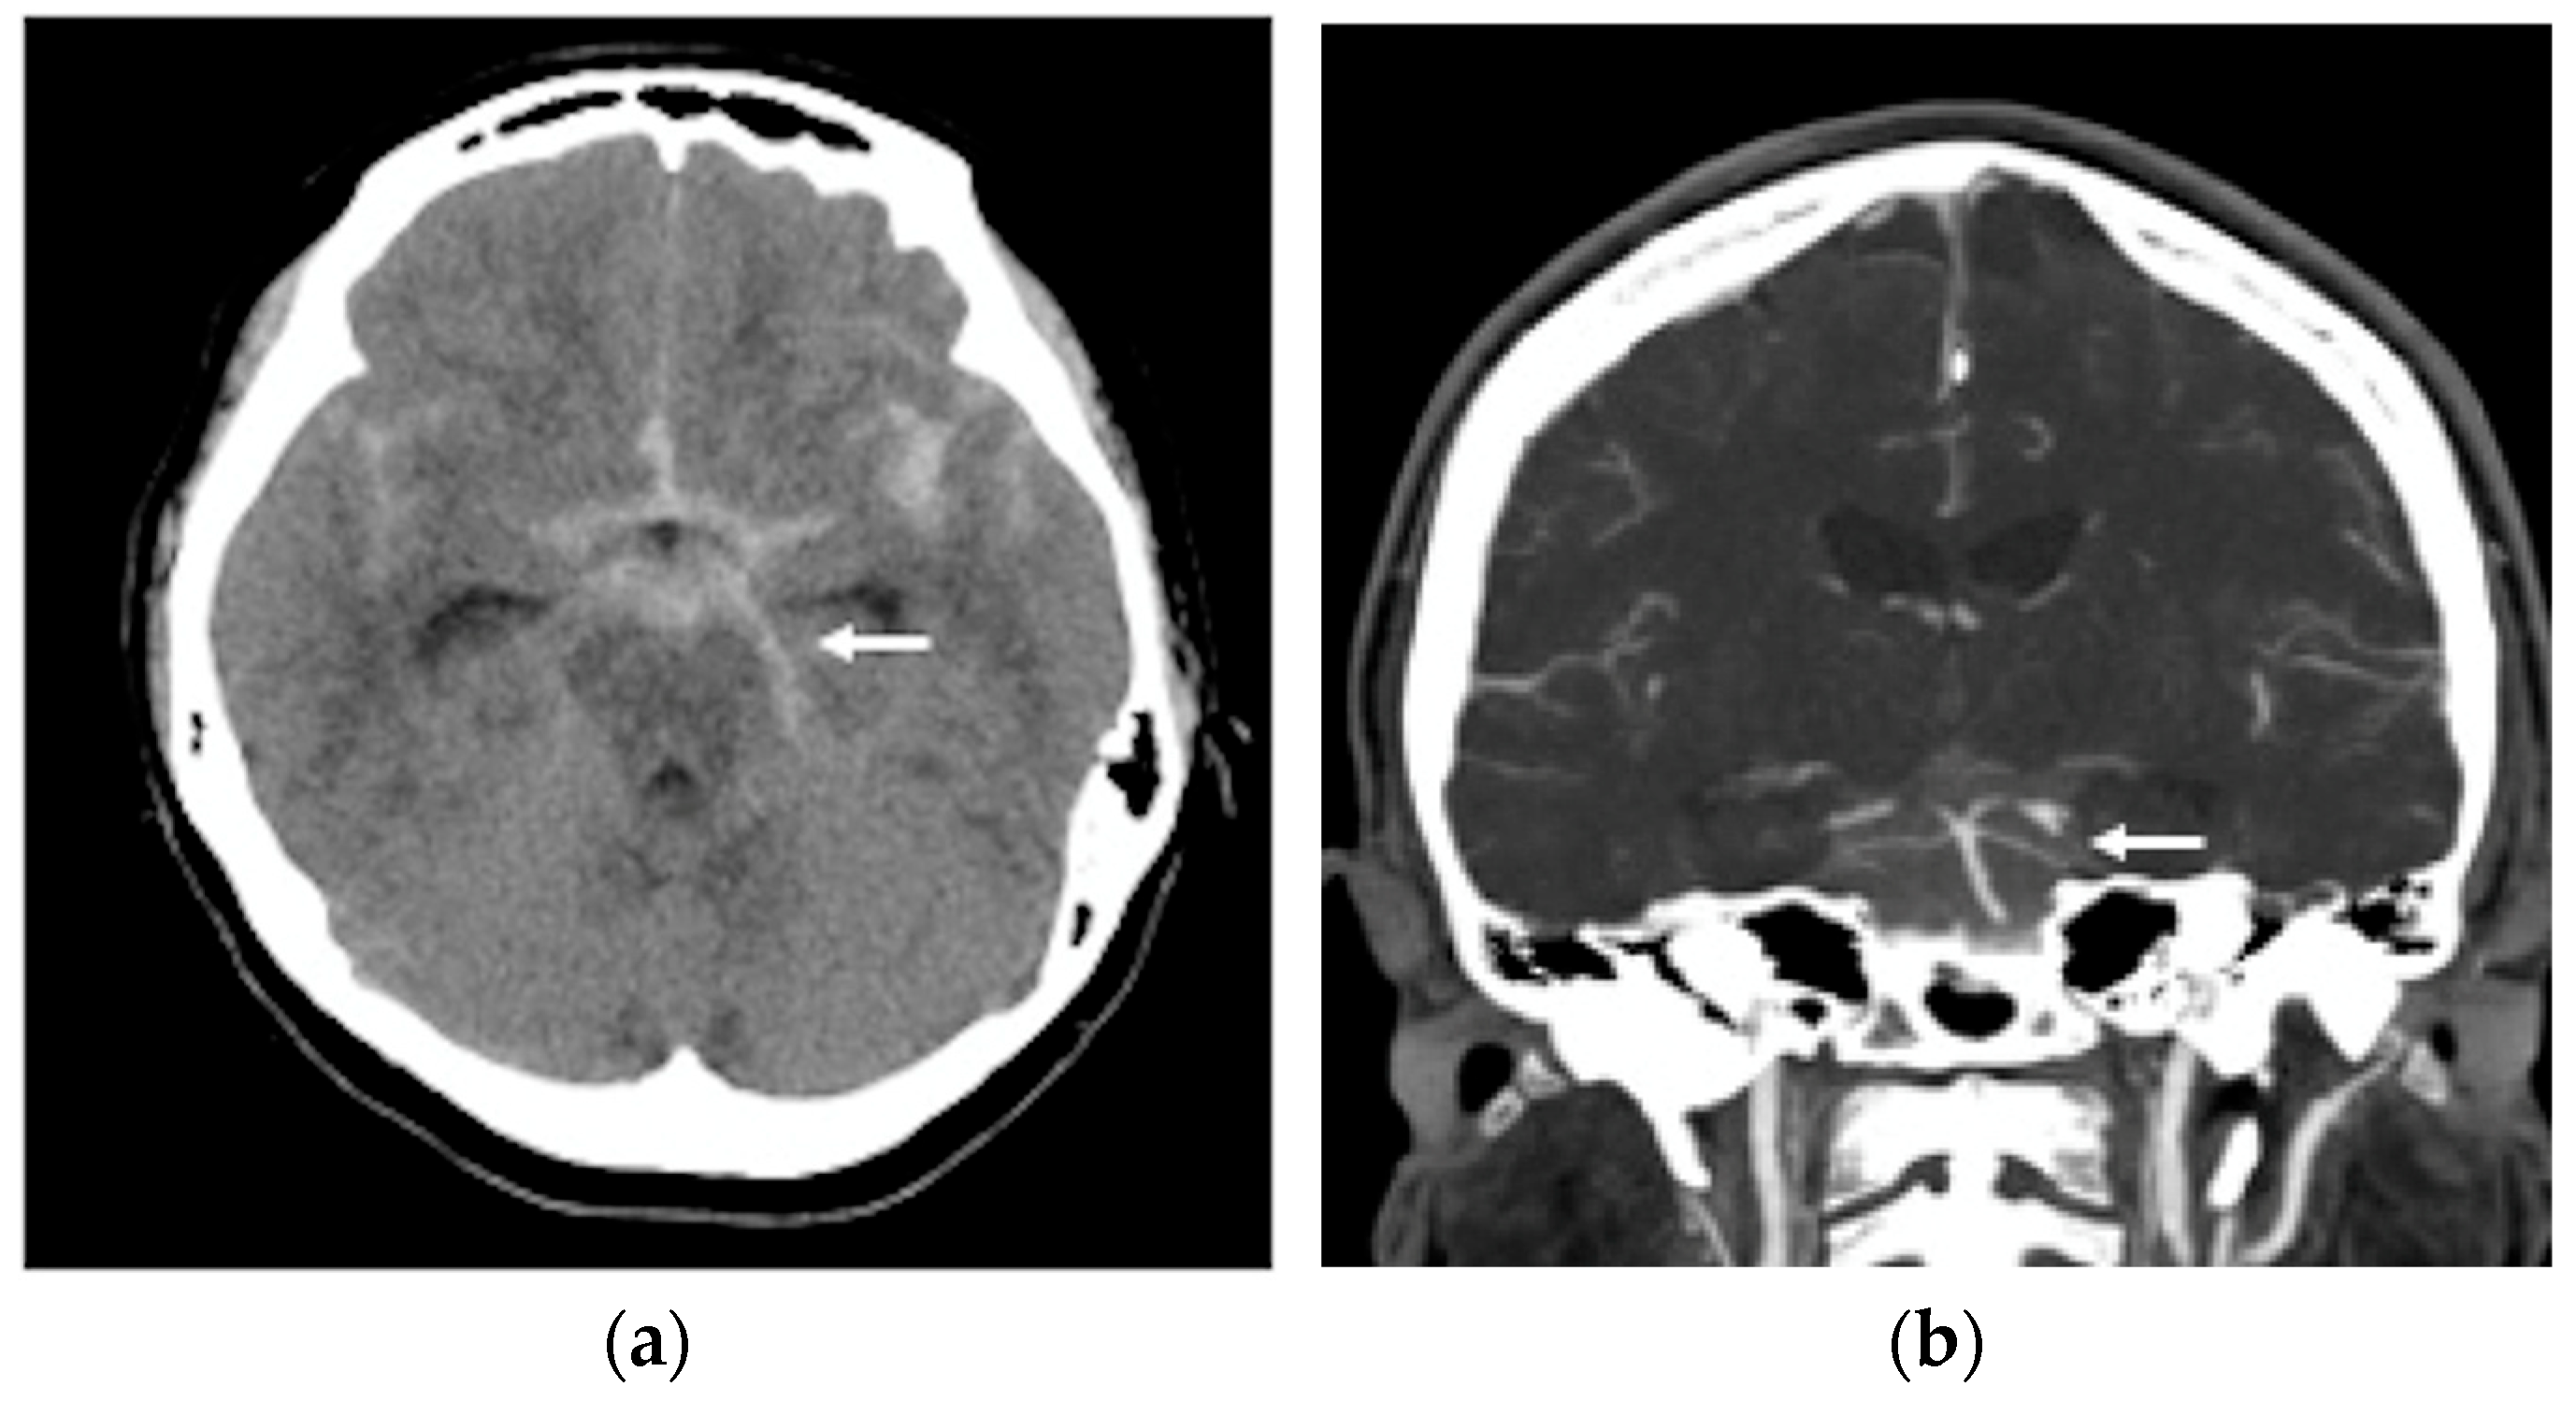

2. Case Report